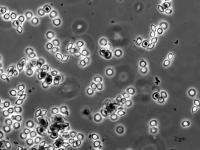

| Species Name: | Aspergillus spinulosporus |

| Taxonomy: | FUNGI Ascomycota, Eurotiomycetes, Eurotiales, Aspergillaceae |

| Substrate: | left occipital brain biopsy, female 21 yr, who had a small bowel transplant 10 yr prior; histopathology + for Aspergillus-like hyphae | Location: | USA Nebraska, Omaha, University of Nebraska Medical Center (GEO: 41.255,-95.976) |

| Characters: | CULTURE CONDITIONS heavy ascomata on PDA - // HUMAN/ ANIMAL PATHOGEN cerebral aspergillosis in a small bowel transplant patient - // MOLECULAR SYSTEMATICS calmodulin sequence has 99% identity to 5 strains of E. echinulata in the GenBank - fide P. Iwen (Click for publications citing UAMH 10948) |